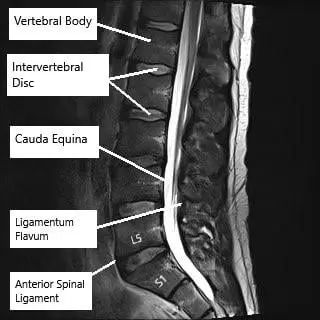

Resonancia magnética de la columna lumbar en corte axial y sagital

Resonancia magnética de la columna lumbar en corte axial y sagital.

Visión general de la imagen

Las radiografías proporcionan una visualización básica de la alineación de la columna vertebral y la integridad ósea. Los TAC ofrecen imágenes detalladas de las estructuras óseas y son útiles en traumatismos o afecciones degenerativas. La RM es la mejor herramienta de diagnóstico por imagen para evaluar los tejidos blandos, incluidos los discos intervertebrales, los ligamentos, las raíces nerviosas y la médula espinal.

La resonancia magnética también puede mostrar hernias discales, compresión nerviosa y cambios postoperatorios, como la colocación de una prótesis discal cervical, un implante que restablece el movimiento en un segmento vertebral enfermo.